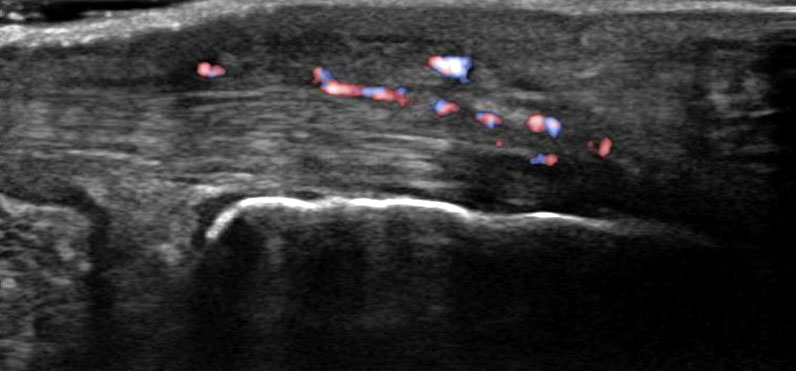

Hier befindet sich ca. 3-5 cm proximal des Tuber calcanei ein als „kritische Zone“ benannter Bezirk, der durch eine ungünstige arterielle Blutzufuhr gekennzeichnet ist (letzte Wiese). Hier finden sich häufig spindelförmige Schwellungen, die bei MRT-Diagnostik nicht selten partielle Nekrosen und Partialrupturen der Achillessehne aufweisen (Abb. 14).

Unabhängig davon können insbesondere chronische Insertionstendinosen der Achillessehne von Partialrupturen (Abb. 15) und erosiven Läsionen des dorsalen Fersenbeines begleitet sein.

Die sonographische Diagnostik eignet sich primär zur Erkennung schmerzhafter Prozesse im Verlauf der Achillessehne und kann bei Bedarf durch Röntgen bzw. MRT ergänzt werden. Besonders bei längeren Verläufen und kräftigen spindelförmigen Schwellungen (>9mm, Normwert <5mm) im Bereich der kritischen Zone sollte ein MRT zum Ausschluss von Nekrosezonen und Partialrupturen vor Therapiebeginn veranlasst werden. Die sonographisch leicht zu erfassende Veränderung der Sehnendicke im mittleren Sehnenanteil ist ein guter Indikator für die Schwere der Erkrankung und die Beurteilung des Behandlungsverlaufes. Die sichtbaren Veränderungen am distalen knöchernen Ansatz der Sehne sind diskreter.

Insbesondere bei größeren Partialrupturen (Abb. 14) sollten operative Verfahren erörtert werden. Kleinere Partialrupturen sind der ESWT gut zugänglich, wie die beiden nachfolgenden Beispiele zeigen: